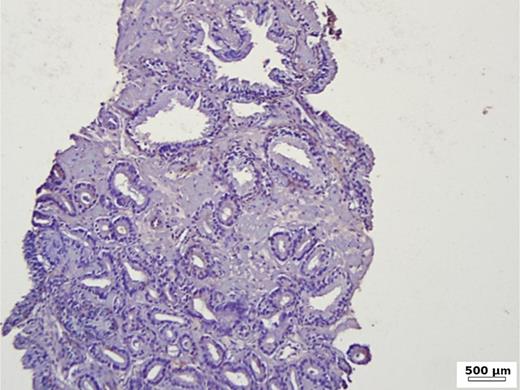

In the group of patients without carcinoma, the vast majority exhibited BSP expression of less than 1%. Twenty-nine out of thirty patients had a value below 5% (Table 1). One patient showed a BSP expression of 9%; however, the expression was observed only in basal cells in a condition of basal cell hyperplasia combined with chronic inflammation (Fig. 1). BSP expression in prostate tissue without carcinoma and without basal cell hyperplasia is shown in Figure 2.

Fig. 2.

Immunohistochemistry in prostate tissue without carcinoma and without basal cell hyperplasia.